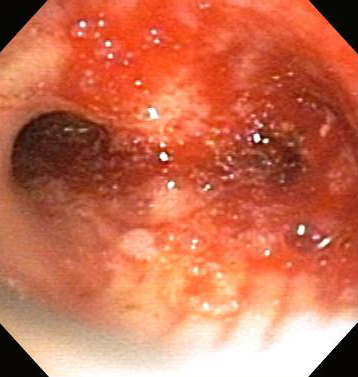

Бронхоскопическая терапия для обструкции нижних дыхательных путей правого главного бронха: постмеханическая циторедукция

Из коллекций Хосе Фернандо Сантакруза, дипломированного врача, члена Американской коллегии специалистов в области торакальной медицины, DAABIP, и Эрика Фолка, дипломированного врача, магистра наук; используется с разрешения